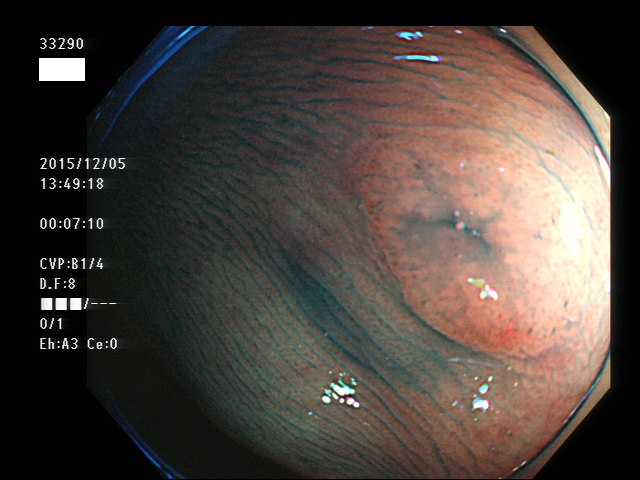

上記100名より抽出した平坦・陥凹型腺腫(=癌化の危険が高いが見落としやすい病変)の内視鏡写真